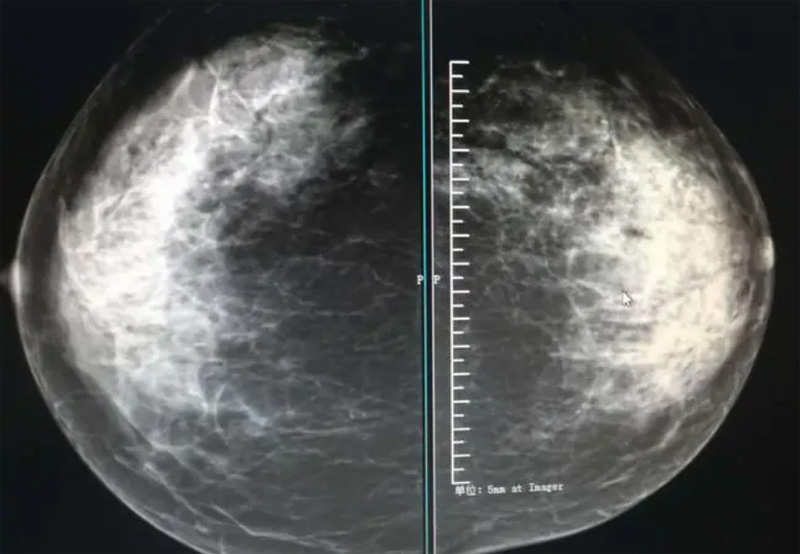

乳腺DR攝影體位有頭尾位及內外側斜位,

乳房在片子的中央,乳頭切線位,可見小部分胸大肌,內側乳腺組織應全部包括在片中,外側乳腺組織盡可能包括在片中。一張好的MLO位圖像顯示如下:乳房被推向前上,乳腺實質充分展開,胸大肌可見,較鬆弛,下緣達到乳頭水平,乳頭在切線位,部分腹壁包括在片中,但與下部乳腺分開,絕大部分乳腺實質顯示在片中。乳腺組織外緣可見乳頭的輪廓;乳腺後方的脂肪組織被很好地顯示出來,乳房無皺褶。對於CC位及MLO位顯示不良或未包全的乳腺實質,可以根據病灶位置的不同選擇以下體位:外內側位(LM)、內外側位(ML)、內側頭尾軸位(MCC)、外側頭尾軸位(LCC),尾葉位(CLEO)及乳溝位。在臨床實踐中,對於常規體位上發現的異常改變,可以進一步采取一些特殊的攝影技術,包括局部加壓攝影、放大攝影或局部加壓放大攝影技術。

2、規範觀圖程序:屏幕軟閱讀或在專用日光觀片燈下膠片閱讀,後者應同時準備白熾強光燈及觀片放大鏡。注意雙側乳腺配對觀察,推薦雙眼橫向掃描,進行雙乳相同部位圖像比較分析。

3、乳腺實質背景的確定:觀察乳腺實質與脂肪的構成比例,了解乳腺實質類型,以判斷對某些乳腺攝影征象敏感性的影響,有利於確定乳腺攝影對疾病的診斷價值。

必須指出的是,美國放射學會提出的乳腺影像報告和數據係統(Breast Imaging Reporting and Data System, BI-RADS)將乳腺分為4型:脂肪型(乳腺內幾乎全部為脂肪組織,腺體組織占25%以下)、少量腺體型(乳腺內散在腺體組織,大約占25%~50%)、多量腺體型(乳腺呈不均勻致密表現,腺體組織大約占51%~75%)、致密型(乳腺組織非常致密,腺體組織占75%以上)。這種分型的主要意義在於說明X線對不同乳腺類型中病變檢出的敏感性不同,對發生在脂肪型乳腺中病變的檢出率很高,而對發生在致密型乳腺中病變的檢出率則有所降低,臨床醫師了解這一點很重要。